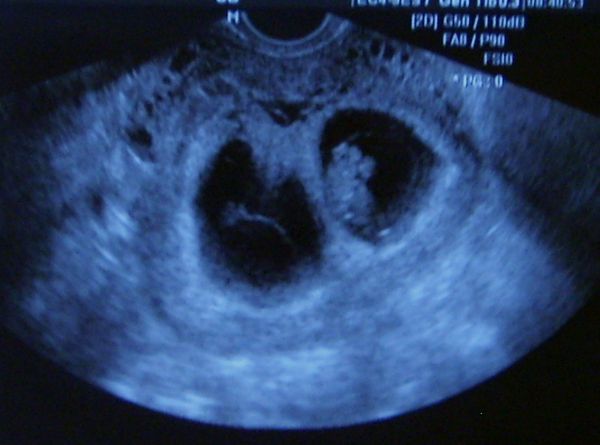

Nagyon rossz, mert ugyan már a 12. héten vagyok, de még mindig vannak rosszabb napjaim, amikor szurkál, fájdogál a hasam. Nagyon-nagyon megtudok retteni ettől..már kezd elegem lenni az örökös aggodalmaskodásból...

Az elején másik dokim volt 6. héten váltottam..mert állandóan kérdésekkel teli jöttem ki tőle..soha nem világosított fel az aktuális kérdések meg bennem maradtak! Megválaszolatlanul.. Ő csak azt mondta a hasszurkálásra, hogy fenyegető vetélés! Ennek már 6. hete!